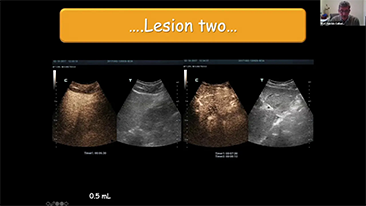

Bir karaci?er ne kadar net g?rĂŒlebilir?

Hemanjiyom veya karaci?er kanseri gibi fokal karaci?er lezyonlar? i?in, ultrason kontrast g?rĂŒntĂŒlemesi ?nemli bir rol oynar. Ultra geni? lineer olmayan UWN+ kontrast g?rĂŒntĂŒleme teknolojisi, daha dĂŒ?ĂŒk MI ve daha uzun perfĂŒzyon sĂŒresi g?zlemi ile daha iyi penetrasyon, daha yĂŒksek kontrast doku oran? elde edilmesine yard?mc? olabilir.